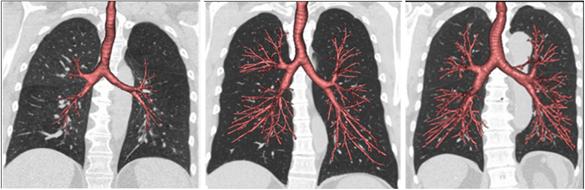

image: These CT scans of airways (red) and lungs (black) show the spectrum of dysanapsis, with smaller airways in proportion to lung size (left) compared with normal size airways (middle), and larger than normal airways (right).

When people breathe, they move air through their airways, beginning with the windpipe or trachea, which branches out to smaller airways called bronchi and bronchioles. As people grow, their airways are thought to develop in proportion to their lungs, but in some people, the airways grow smaller or larger than expected--a condition called dysanapsis-- for reasons that are not clear.

In the MESA Lung and CanCOLD studies, participants with smaller airways relative to lung size were much more likely to develop COPD compared with those with the larger airways relative to lung size. The association remained after considering standard COPD risk factors, including smoking, pollutants, and asthma.

The researchers then focused on participants from the CanCOLD study who never smoked and heavy smokers from the SPIROMICS study. Never smokers with COPD had much smaller airways relative to lung size, whereas the heavy smokers who did not have COPD had larger than normal airways.